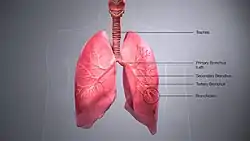

A bronchus is a passage or airway in the lower respiratory tract that conducts air into the lungs. The first or primary bronchi (pronounced BRAN-KAI) to branch from the trachea at the carina are the right main bronchus and the left main bronchus. These are the widest bronchi, and enter the right lung, and the left lung at each hilum. The main bronchi branch into narrower secondary bronchi or lobar bronchi, and these branch into narrower tertiary bronchi or segmental bronchi. Further divisions of the segmental bronchi are known as 4th order, 5th order, and 6th order segmental bronchi, or grouped together as subsegmental bronchi.[1][2] The bronchi, when too narrow to be supported by cartilage, are known as bronchioles. No gas exchange takes place in the bronchi.

The trachea (windpipe) divides at the carina into two main or primary bronchi, the left bronchus and the right bronchus. The carina of the trachea is located at the level of the sternal angle and the fifth thoracic vertebra (at rest).

The right main bronchus is wider, shorter, and more vertical than the left main bronchus,[3] its mean length is 1.09 cm.[4] It enters the root of the right lung at approximately the fifth thoracic vertebra. The right main bronchus subdivides into three secondary bronchi (also known as lobar bronchi), which deliver oxygen to the three lobes of the right lung—the superior, middle and inferior lobe. The azygos vein arches over it from behind; and the right pulmonary artery lies at first below and then in front of it. About 2 cm from its commencement it gives off a branch to the superior lobe of the right lung, which is also called the eparterial bronchus. Eparterial refers to its position above the right pulmonary artery. The right bronchus now passes below the artery, and is known as the hyparterial branch which divides into the two lobar bronchi to the middle and lower lobes.

The left main bronchus is smaller in caliber but longer than the right, being 5 cm long. It enters the root of the left lung opposite the sixth thoracic vertebra. It passes beneath the aortic arch, crosses in front of the esophagus, the thoracic duct, and the descending aorta, and has the left pulmonary artery lying at first above, and then in front of it. The left bronchus has no eparterial branch, and therefore it has been supposed by some that there is no upper lobe to the left lung, but that the so-called upper lobe corresponds to the middle lobe of the right lung. The left main bronchus divides into two secondary bronchi or lobar bronchi, to deliver air to the two lobes of the left lung—the superior and the inferior lobe.

The secondary bronchi divide further into tertiary bronchi, (also known as segmental bronchi), each of which supplies a bronchopulmonary segment. A bronchopulmonary segment is a division of a lung separated from the rest of the lung by a septum of connective tissue. This property allows a bronchopulmonary segment to be surgically removed without affecting other segments. Initially, there are ten segments in each lung, but during development with the left lung having just two lobes, two pairs of segments fuse to give eight, four for each lobe. The tertiary bronchi divide further in another three branchings known as 4th order, 5th order and 6th order segmental bronchi which are also referred to as subsegmental bronchi. These branch into many smaller bronchioles which divide into terminal bronchioles, each of which then gives rise to several respiratory bronchioles, which go on to divide into two to eleven alveolar ducts. There are five or six alveolar sacs associated with each alveolar duct. The alveolus is the basic anatomical unit of gas exchange in the lung.